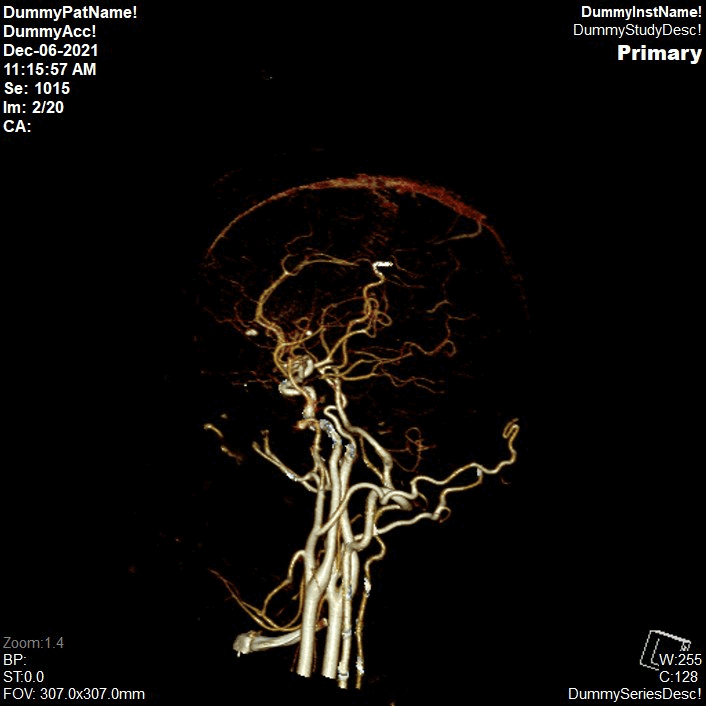

Appearance of Cerebral Artery in Neuro DSA CT Image

Multiplanar Reconstruction (MPR)

Siemens SyngoVia 3D Rendering

Volume Rendering Technique

- Circle of Willis

- Radial Ranges

- Rotate: 19 images

- Tumble: 19 images

Open with āCT neuro DSAā.

Rotate and punch.

Select āEdit Bonesā.

Locate and mark the area that was cut along the vessel.

Open āRange Toolsā choose āRadial Rangeā

Radial Range:

Number of images = 19 (lock)

Angle between images= 19

Orientation:

Start from AP view. Then click āStartā

Save as VRT CTA Brain